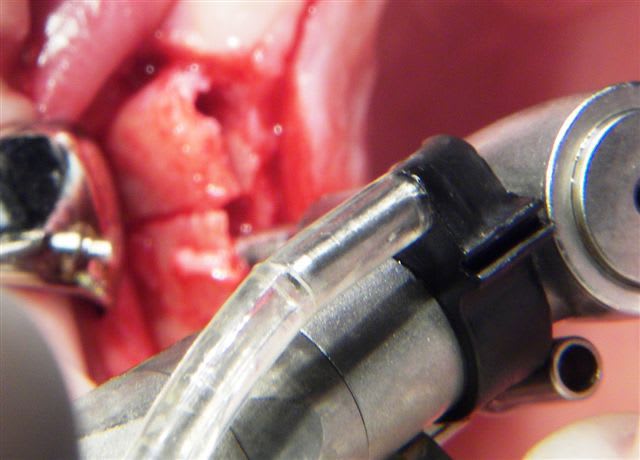

Serrage manuel, sans lambeau. Extraction implantation immédiate

le 4.5*11 me semblait convenable. J'avais peur que si je metais du 4*11 l'espace entre les cretes vestibulaires et l'implant allait creer une recession si je ne comblait pas ce vide

Rappelons qu'en mesurant j'ai 1.25 mm d'os au final et pas 0.5-0.8mm

merci pour tes réponses, pour ma part (expérience avec plus de 600 implantation immédiate) je ne pense pas qu'il va y avoir une résorption, car pas de lambeau et tu n'as pas mis de trop grande pression sur l'os buccal.Un exemple ci dessous implantation ( 4 semaines après extraction) avec un 4.5 que (oui déjà mis dans un autre post).J'ai d'autres exemples similaires en extraction implantation immédiate mais avec des implants 3.5mm.Si l'espace entre l'implant et l'os buccal est plus grand que 1mm j'ajoute du collagène et de l'acide hyaluronique pour accélérer la régénération.

Ce qui est non négligeable est d'avoir une stabilité primaire d'un minimum de 35Ncm et pas plus de 70Ncm.